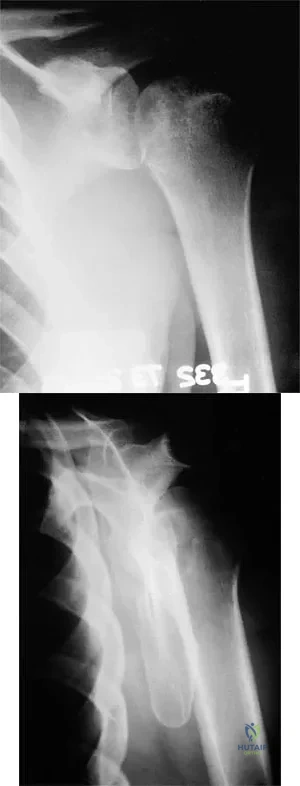

A 55-year-old man sustained an isolated closed fracture of the humerus. Initial neurologic examination reveals no active wrist or finger extension. Radiographs are shown in Figures 28a and 28b. Management should consist of

The patient has an isolated closed injury involving the humeral diaphysis. The lack of wrist and finger extension indicates injury to the radial nerve. Based on these findings, ongoing observation of the nerve is warranted with delayed exploration after 3 to 4 months if there are no signs of progressive return of nerve function. Treatment of the fracture should include external immobilization and fracture bracing. An indication for nerve exploration and surgical stabilization would be an open fracture. Zuckerman JD, Kovil KJ: Fractures of the shaft of the humerus, in Rockwood CA Jr, Green DP, Bucholz RW, Heckman JD (eds): Rockwood and Green's Fractures in Adults, ed 4. Philadelphia, PA, Lippincott-Raven, 1996, pp 1025-1053.